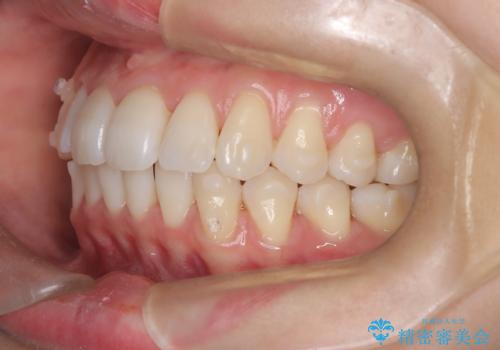

インビザラインモデレートによる前歯の叢生改善|IPR最小限で自然な歯並びへ

- 患者様は、**前歯の叢生(がたつき)**を気にされて来院されました。

できるだけ歯を削らずに、自然な歯並びを手に入れたいというご希望がありました。

診査の結果、中等度の叢生であったため、インビザラインモデレートでの対応が可能と判断しました。

歯へのダメージを抑えるため、IPR(歯間削合)は必要最小限にとどめる方針としました。

前歯の叢生は解消され、自然で調和の取れた歯並びが得られました。

「歯をほとんど削らずにきれいになった」と、患者様にもご満足いただけました。